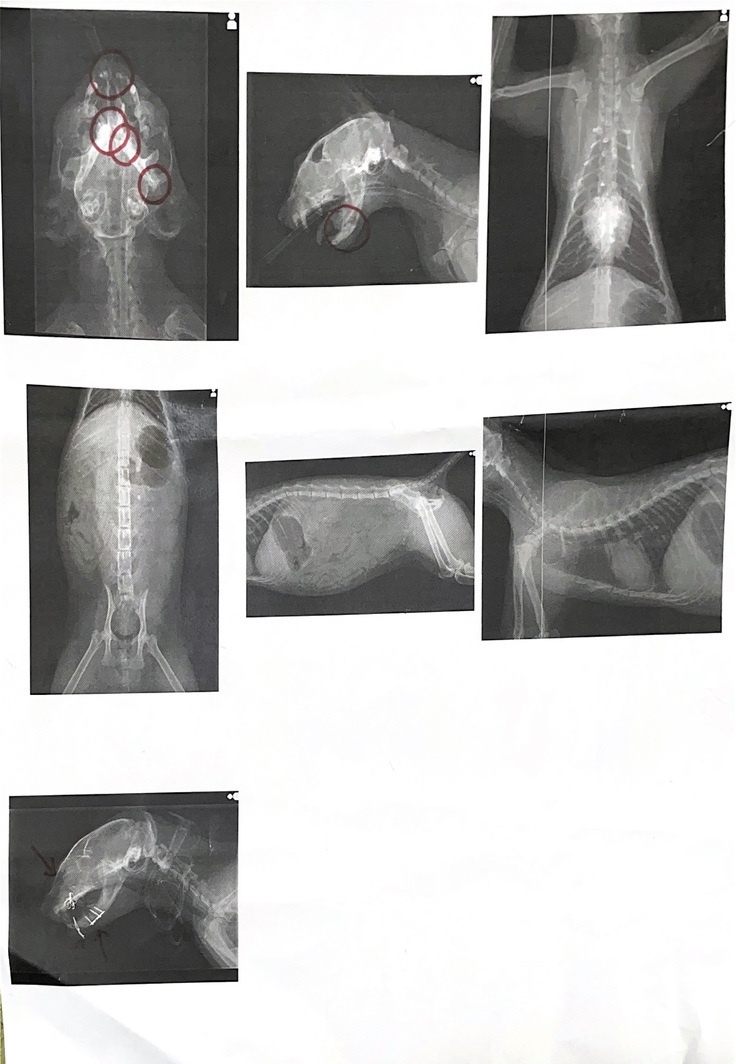

検査の結果下顎の骨が砕けている、耳から顎にかけての関節円板が外れている?レントゲンでは分からない様子。

左右の瞳孔の開きの違いから脳挫傷との判断。

身体は目立った外傷なし、内臓の傷もレントゲンでは確認できず。

頭蓋骨が縦に深く割れており、右顎が砕けて左顎も損傷。

感染の可能性があるものの治療優先で頭蓋骨と下顎に固定器具をつける。

赤いペンで丸く囲ってあるところが外傷箇所です。

時系列がバラバラになって申し訳ありませんが、顎形成中の写真です。

目の横の赤いハゲている部分は怪我した時に出来たかさぶさが取れたものです。

上レントゲン図の赤丸の部分には全て固定器具が埋まっており、顎の固定器具は外に飛び出しており、痛々しいです。猫自身もカラーを取ると痒そうにしています。

顎の粉砕骨折と脱臼で、口から栄養が摂れない為、首にチューブをつけそこから栄養、薬を流し込む。

血液検査、レントゲンで全身の状態を確認。

四肢は何ともなく、内臓も悪いところは無いが、どこからか出血している様で、呼吸時にグルグルと言っている。

両顎(耳の下)の脱臼箇所を自然に閉じたり動かせる様にする為、骨を切断する。